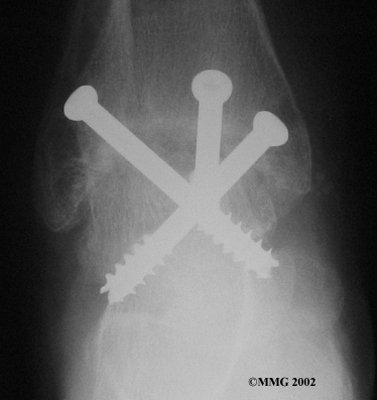

It is important when the surfaces are removed that the angles of the cut surfaces are correct. When the tibia is brought against the talus, the foot should be at a right angle to the lower leg. Once the cuts are made the bones must be held in place while they fuse. This can be done using large metal screws and metal plates if necessary. The screws are usually under the skin and are not removed unless they begin to rub and cause pain.

Inserting the screws

After ankle fusion, the physical therapists at FYZICAL Central Nampa can help you learn to walk smoothly and without a limp. Although time needed for recovery varies among patients, an ankle brace will typically replace your cast after eight to 12 weeks. Your surgeon will take X-rays frequently to see if the bones are fusing together. You will probably need to use crutches during the time you wear the cast. As the fusion grows stronger, you will begin to put more weight on your foot when walking.